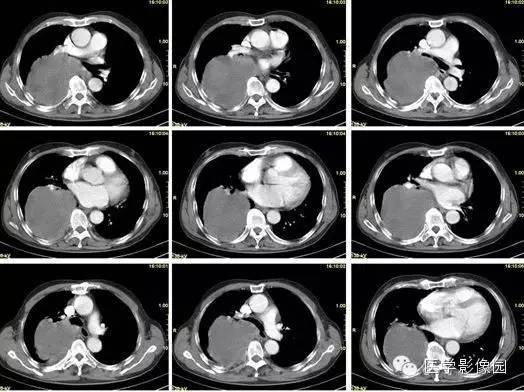

纵隔占位?肺内占位?巨大中央型肺癌1例

【病例】巨大中央型肺癌1例